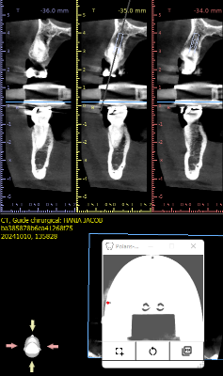

Visualization of the implant axis

The axis defined by the cone beam is materialized directly on the model.

Visualization of the implant axis on the model, accurately confirming the planning on the software.

Visualization of implant axes in reality from two angles, accurately confirming the software planning.